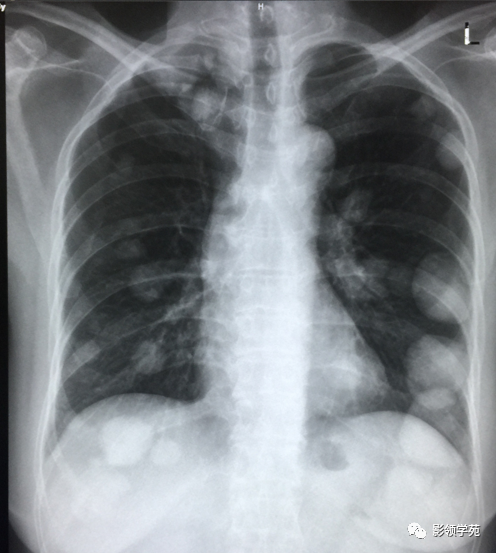

血行转移:双肺多发密度一致、大小形态不一结节状影(下图)

淋巴转移:肺门影增大,自肺门向外部规则索条状影(下图)

双肺淋巴道转移癌。胸部正位片示双侧中下肺野多发结节状及网格状高密度结节影,可见克氏B线(下图)